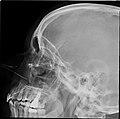

X-ray images and illustrations